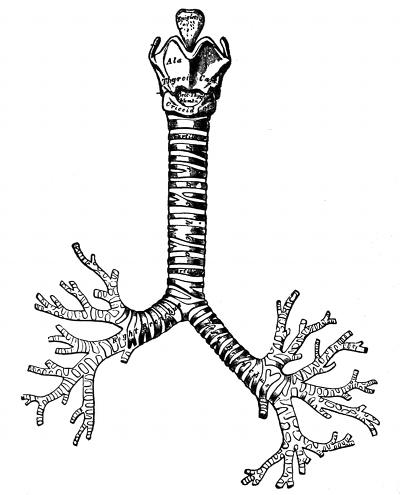

Hyaline cartilage is found in the nose, larynx, trachea,

and bronchi.